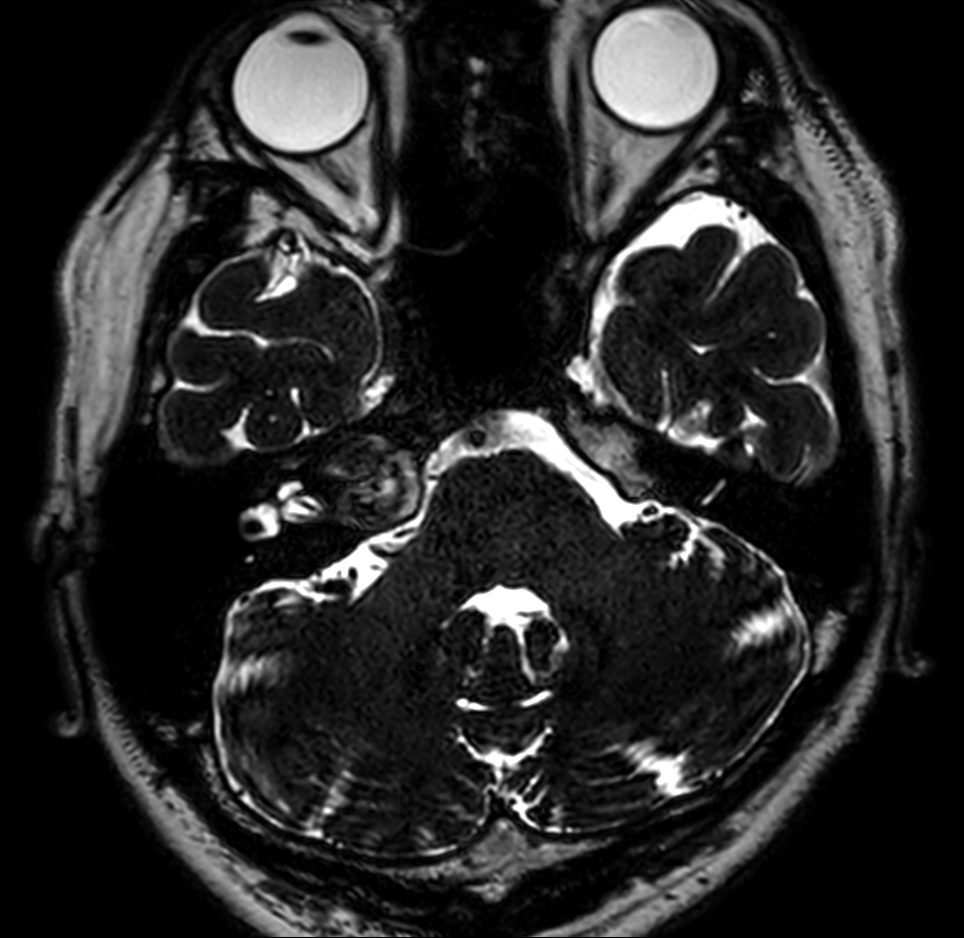

Patient with an IAC lesion. Comparing different DWI methods (EPI, TSE, ZOOM). Compressed SENSE is added to all TSE sequences to decrease scan times, thereby shortening the time the patient has to spent in the magnet. The dS Head 32ch coil is used to enhance image quality.

T2w TSE

3D T2w TSE DRIVE